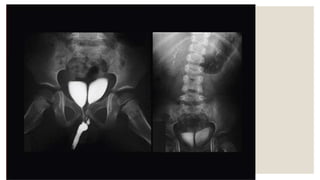

Neurogenic bladder

Crossed renal ectopia is said to be present when the kidney is seen in the

opposite retroperitoneal space.

It is more common for the left kidney to be ectopically located on the right

side.

Patent urachus

represents the failure of the entire

course of the urachus to close

resulting in an open channel

between the bladder and the

umbilicus.

A patent urachus is usually

diagnosed neonates when urine is

noted leaking from the umbilicus.

A patent urachus may present later

in life and it can become infected.

Bladder duplication